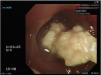

A 63-year-old man with bronchiectasis suffered from respiratory failure status post tracheostomy. He experienced sudden massive hemoptysis requiring an emergent bronchoscopy during admission. After removing a bronchial cast formed by coagulated blood (Fig. 1) in bronchi, no active bleeder was found, and vital signs became stable. However, multiple endobronchial necrotic-like masses containing sulfur granules were found in bilateral sub-branches in the lower bronchi (Fig. 2). The pathological report revealed bacterial colonies with Gram-positive filamentous bacilli and cocci (Fig. 3), suggesting a diagnosis of actinomycosis. Surgical intervention was not recommended after multidisciplinary expert discussion due to poor pulmonary function. The patient received prolonged antibiotic treatment and was successfully weaned from the ventilator.